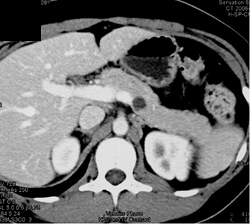

Cystic Lesion in Tail of the Pancreas - Islet Cell